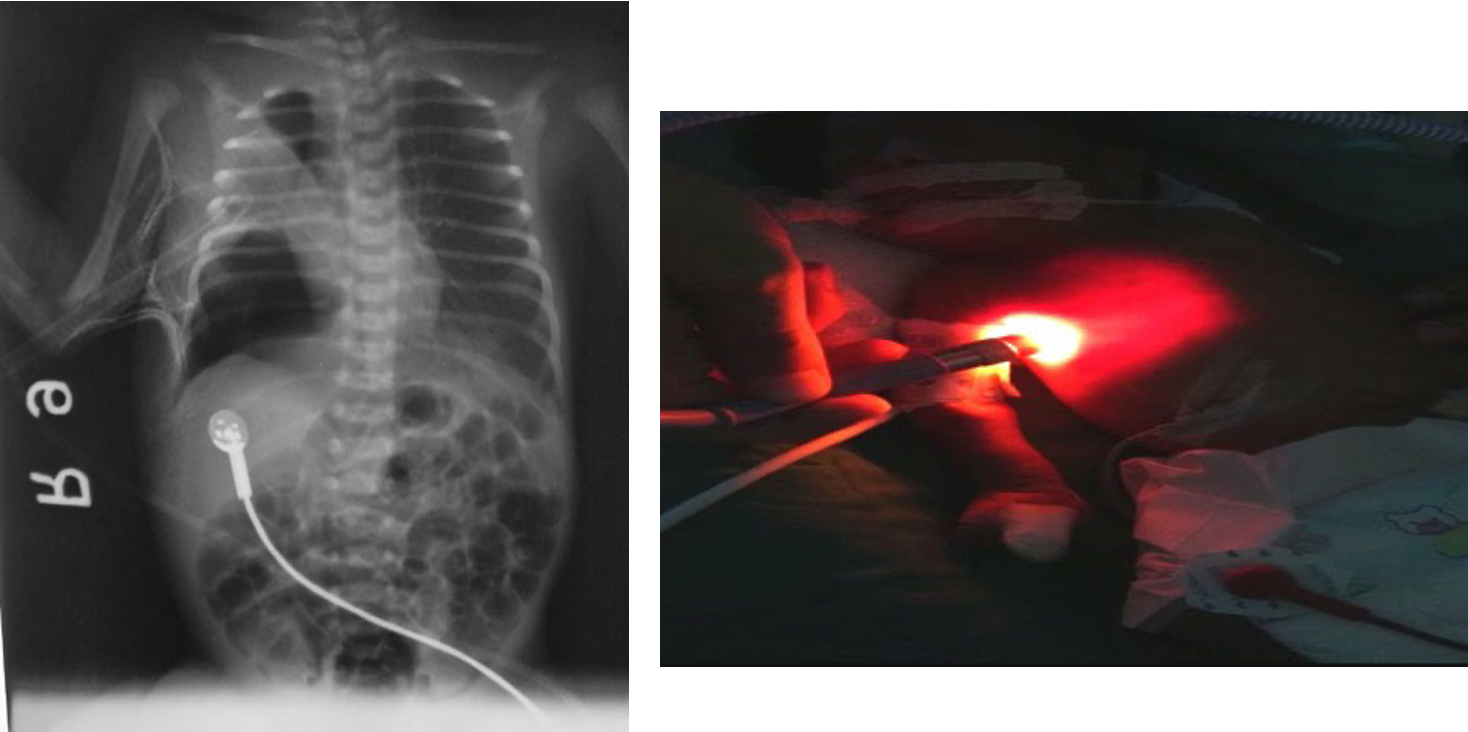

if light goes throughout lung theres pneumothoraxm if localized, its not pneumothorax.

High-intensity fiber optic light demonstrating increased transillumination on the left half of the chest suggestive of left-side pneumothorax compared to the normal right chest.

Deep Sulcus Line

- Notice:

“Deep sulcus line” indicating pneumothorax.